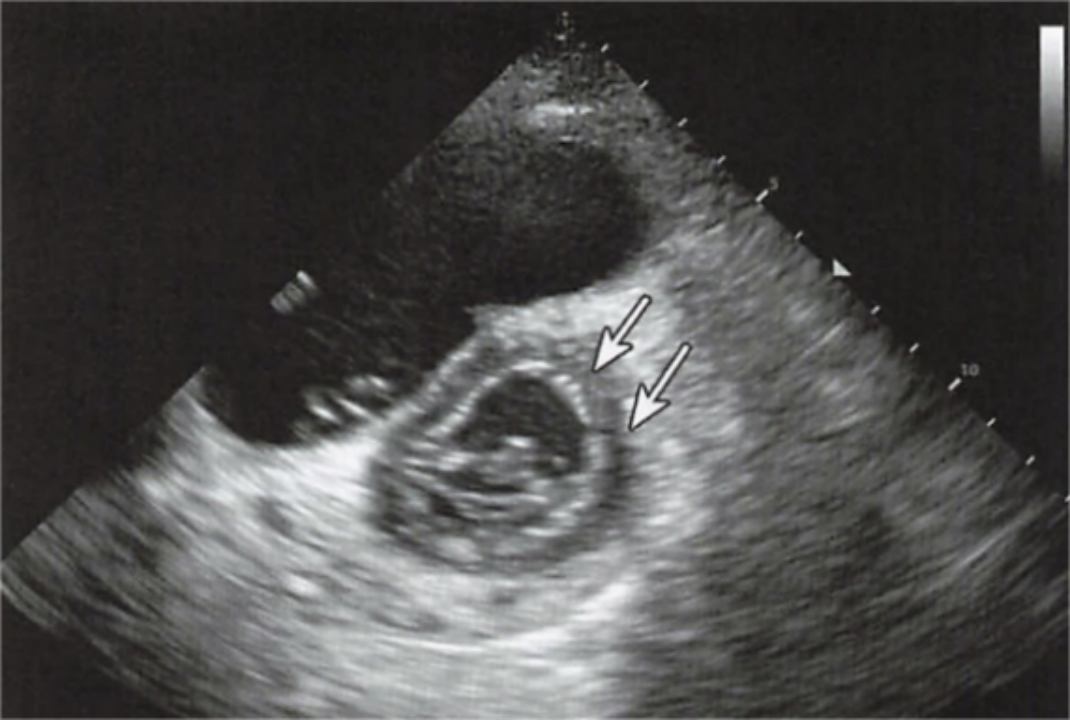

心梗最典型的超声表现就是心肌节段性运动异常。

此外并发症还有室壁瘤形成,血栓形成,室间隔穿孔甚至心脏破裂等。